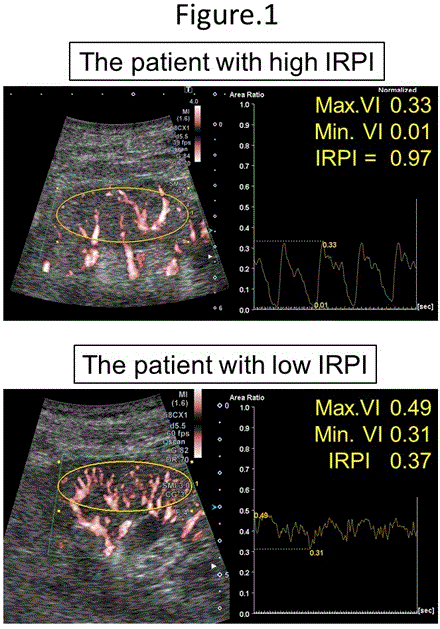

Methods: We retrospectively analyzed 78 patients who underwent renal ultrasonography using SMI from October 2020 to May 2023. We measured changes over time of Vascular Index (VI), which quantifies the blood flow signal area in the region of interest on the SMI image (Figure 1). Key measurements included Maximum VI (Max.VI), Minimum VI (Min.VI), and the cyclic variation of VI, calculated as the intrarenal perfusion index (IRPI) = (Max.VI - Min.VI) / Max.VI within one cardiac cycle. The primary endpoint of this study was a composite event (CE), defined as a composite of all-cause death and unplanned hospitalization for worsening HF.